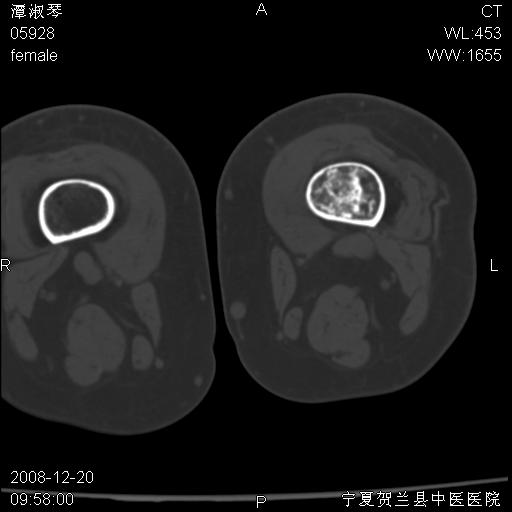

标题: CT17526:请各位看看是啥?

支持骨梗死,退行性骨关节病,膝关节积液.

考虑骨梗死可能性大

骨梗死可能性大

左股骨下段骨梗死。双膝退变。

左胫骨下端松质骨及髓腔内可见点片状高密度灶,骨皮质无明显膨胀及变薄。病变范围较长。支持骨梗死,退行性骨关节病,膝关节积液